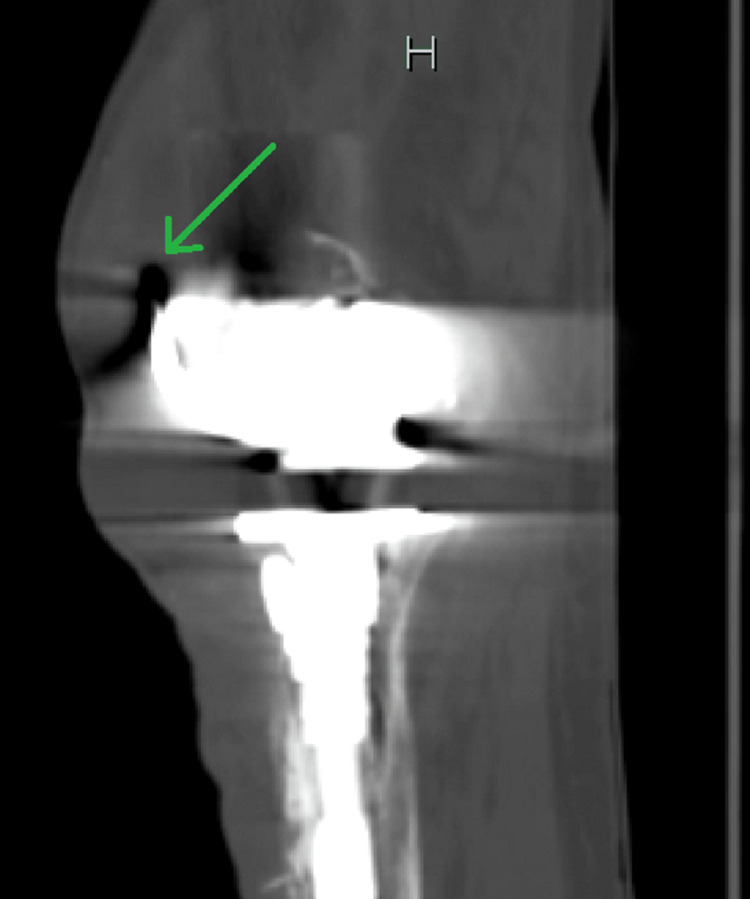

Initial laboratory investigations included a complete metabolic panel (CMP), which was unremarkable, liver function tests within normal limits, and renal function tests (RFTs), which were equally unremarkable with a blood urea nitrogen (BUN) of 21 mg/dL and serum creatinine (sCr) of 0.8 mg/dL. Glucose was 91 mg/dL, and serum calcium was at the upper end of normal, revealing a value of 10.2 mg/dL. Complete blood count (CBC) was remarkable for a significantly elevated white cell count of 28,110 cells/µL, a low hemoglobin level of 12.6 mg/dL, and a low hematocrit of 37%. A urinalysis was also completed and found to be normal as well. Imaging performed included computed tomography (CT) of the lower extremities, which showed a left knee arthroplasty with a long stem prosthesis. These images also revealed a collection of fluid with internal droplets of gas anterior to the knee measuring 8.1 cm × 4.5 cm × 12.3 cm, suggesting an abscess (Figures 1–2). The patient was empirically placed on vancomycin, piperacillin-tazobactam, and morphine.

The patient was then admitted to the hospital where surgery and orthopedics were consulted for further management. The hospitalist obtained further history, which revealed an extensive number of surgeries on the LLE, beginning with a total left knee arthroplasty in 2014. He said it got infected and replaced in 2015 with a Teflon implant. In 2017, there was a second infection, which was treated with two separate instances of antibiotic spacer placement and another replacement of the prosthetic joint. He endorsed a further infection in 2018 where surgery was performed to cut nonviable muscle and place a graft. In total, the patient endorsed having had nine separate surgical procedures on his LLE, with the most recent one in 2018. The last surgeon installed an antibiotic spacer, which was considered a final attempt at saving the limb before considering above-knee amputation. Repeat physical examination revealed the possibility to express grossly purulent drainage from a small ulcer in the lateral portion of the left knee as well as a large soft tissue fluid collection anterior to the joint. Vancomycin was continued, but piperacillin-tazobactam was discontinued and replaced with cefepime based on hospital protocol.

The general and orthopedic surgeons decided an urgent above-knee amputation was necessary, and it was scheduled for the following day. During surgery, a large pocket of pus was encountered anterior to the joint, as delineated by imaging, while separating the soft tissue and collected for culture. The bone had a moth-eaten appearance, and debridement of the medullary cavity of the femur was required with a curette. The surgery was performed by both the general and orthopedic surgeons with no complications other than an estimated blood loss of 50 mL.